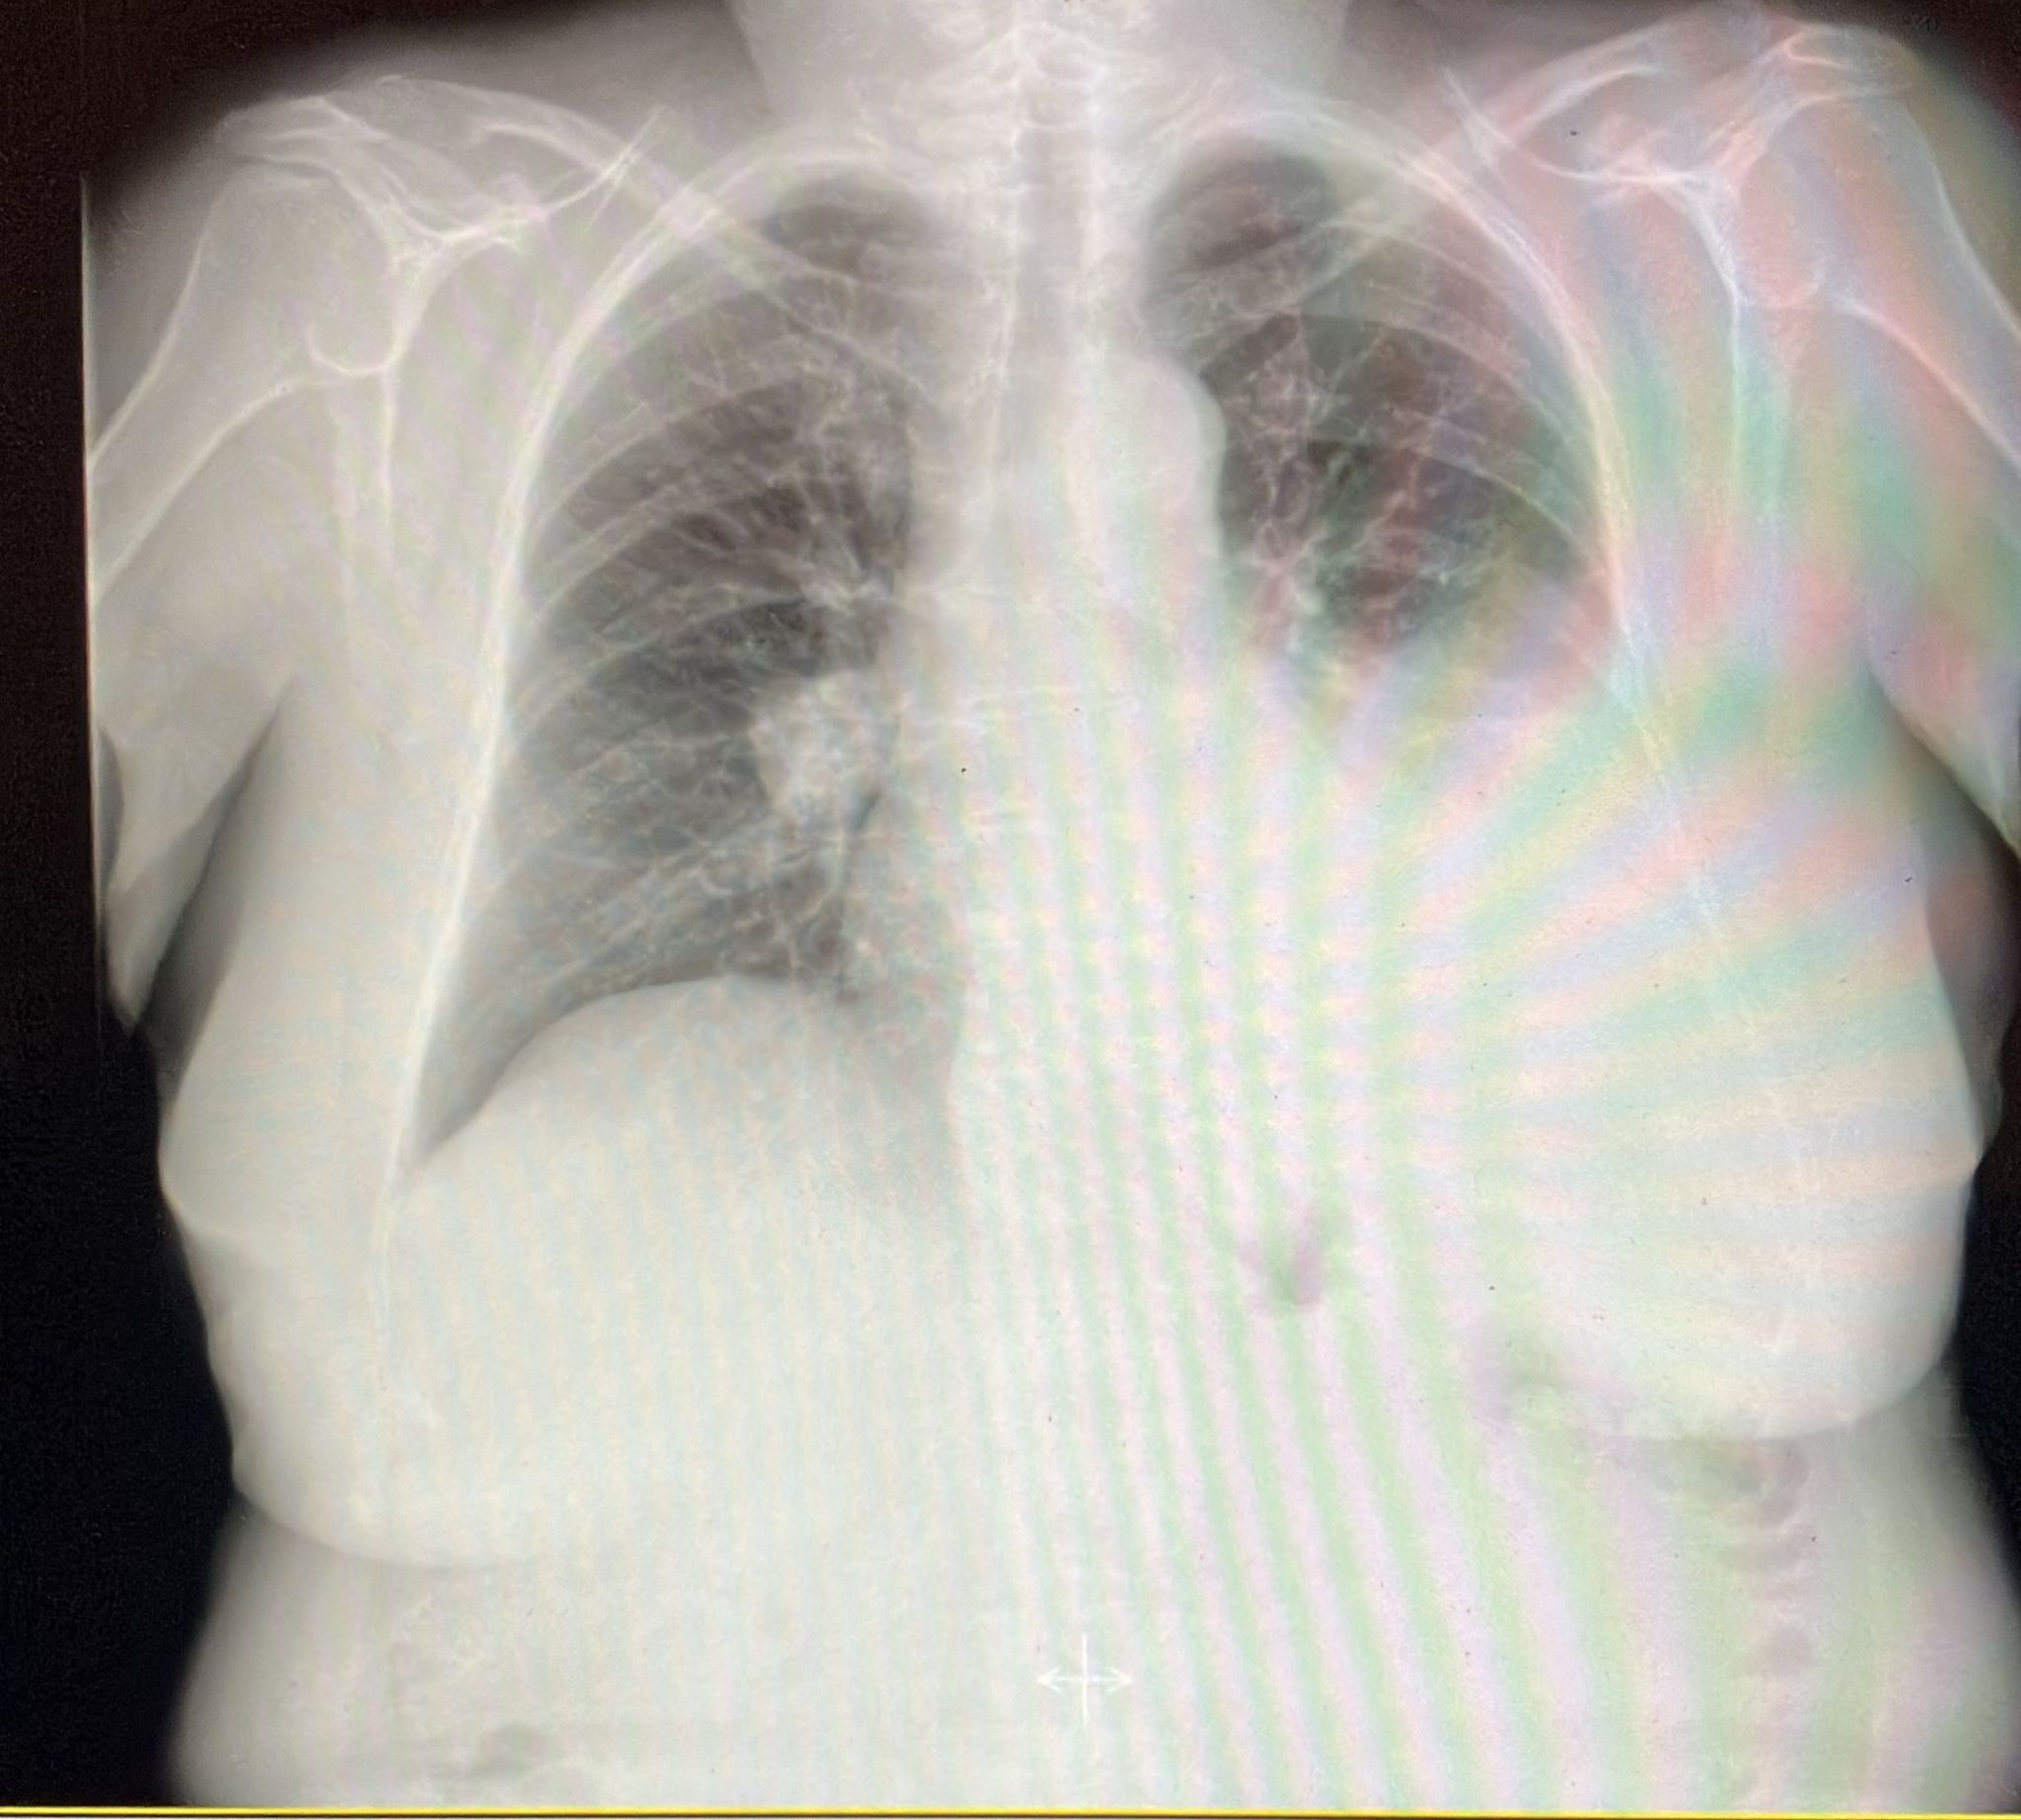

Realizamos RX tórax urgente donde se confirma el derrame pleural unilateral izdo. Derivamos al paciente a urgencias para ingreso a estudio.